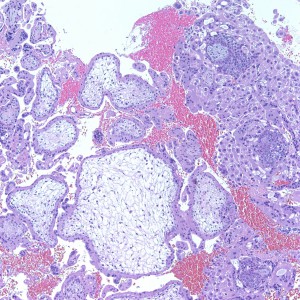

Diagnosis: Complete Hydatidiform Mole

As we can see, enlarged and hydropic chorionic villi are not especially difficult to find (circle). None of these villi however demonstrate trophoblastic inclusions. There are rare interspersed small chorionic villi (top left) however they are generally rare.

Some villi are so large and hydropic that a few have actually developed central cisterns, spaces within the center of the villi (space highlighted by horizontal lines).

This large hydropic villus with central cistern also demonstrates an important finding: the loss of polarity of the surrounding trophoblasts with circumferential proliferation of variably atypical trophoblastic cells (arrows).